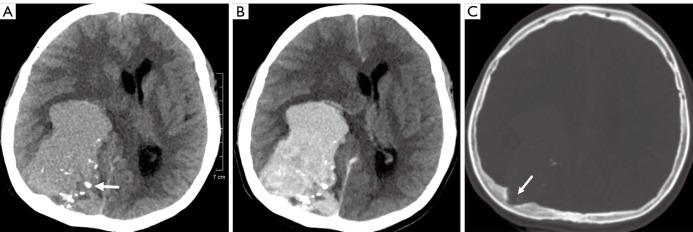

The patient was admitted to our hospital due to headache and dizziness for two months, without nausea, vomiting, limb convulsions and loss of consciousness during the illness. Pre-contrast computed tomography (CT) revealed a large slightly hyperdense mass with irregularly lobulated margins in the right parietal and occipital region and multiple patchy calcifications in peripheral of the lesion. The inner table of right parietal bone adjacent to the mass was compressed, thickened, and eroded. Magnetic resonance imaging (MRI) exhibited intermediate and hypo-intensity on T1-weighted images (TWI) and slight hyper-intensity on T2-weighted images (TWI) with extremely high intensity rim of cerebral spinal fluid (CSF) and low intensity flow-void vessel. The mass demonstrated heterogeneous remarkable enhancement and "dural tail" sign also was noted. The important imaging signs of this case are irregular calcifications of soft tissue on CT and "dural tail" sign on MRI. The patient underwent tumor resection and was followed up postoperatively with serial MRI every three months. He was alive without obvious clinical symptoms and evidence of recurrence for 9 months. EMCS is a highly invasive tumor and it is difficult to differentiate EMCS from the other intracranial malignant tumors only by clinical characteristics or findings of CT and conventional MR imaging. Radiotherapy and chemotherapy after radical resection are the best treatment choice. Therefore, postoperative patients should be reviewed routinely.